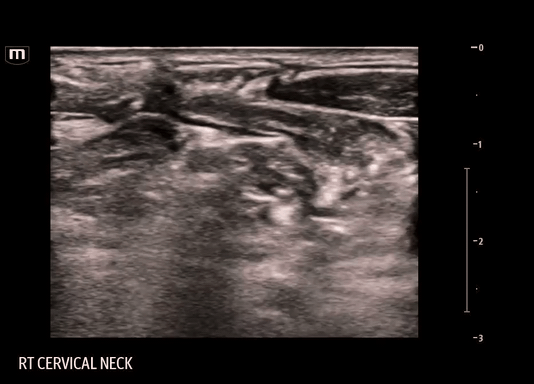

• Using a linear probe, start scanning over the SCM at the level of the thyroid cartilage and slide laterally until visualization of the edge of the sternocleidomastoid muscle (SCM), underlying levator scapulae (LS) muscle, internal jugular vein (IJV) and carotid artery (CA)

• SCP nerve bundle may or may not be present below the SCM

• This procedure is done with in-line technique and the target is the fascial plane just deep to the SCM and superficial to the prevertebral fascia containing the LSM and scalene muscles.

Clips from our block:

FYI: During this particular block, the needle entered from the same side as the SCM, contrary to the usual technique. This was done to avoid a vessel on the other side. The block should routinely be done as described above.